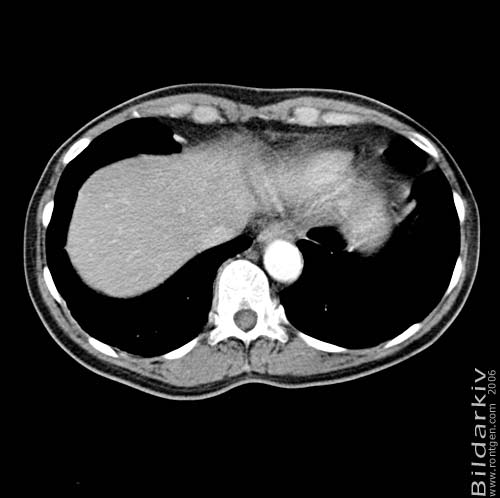

Thorax 47

Snitt över thorax med kontrast. Sk. mediastinum-fönstersättning.

CT Röntgen Helsingborgs lasarett

Mediastinum